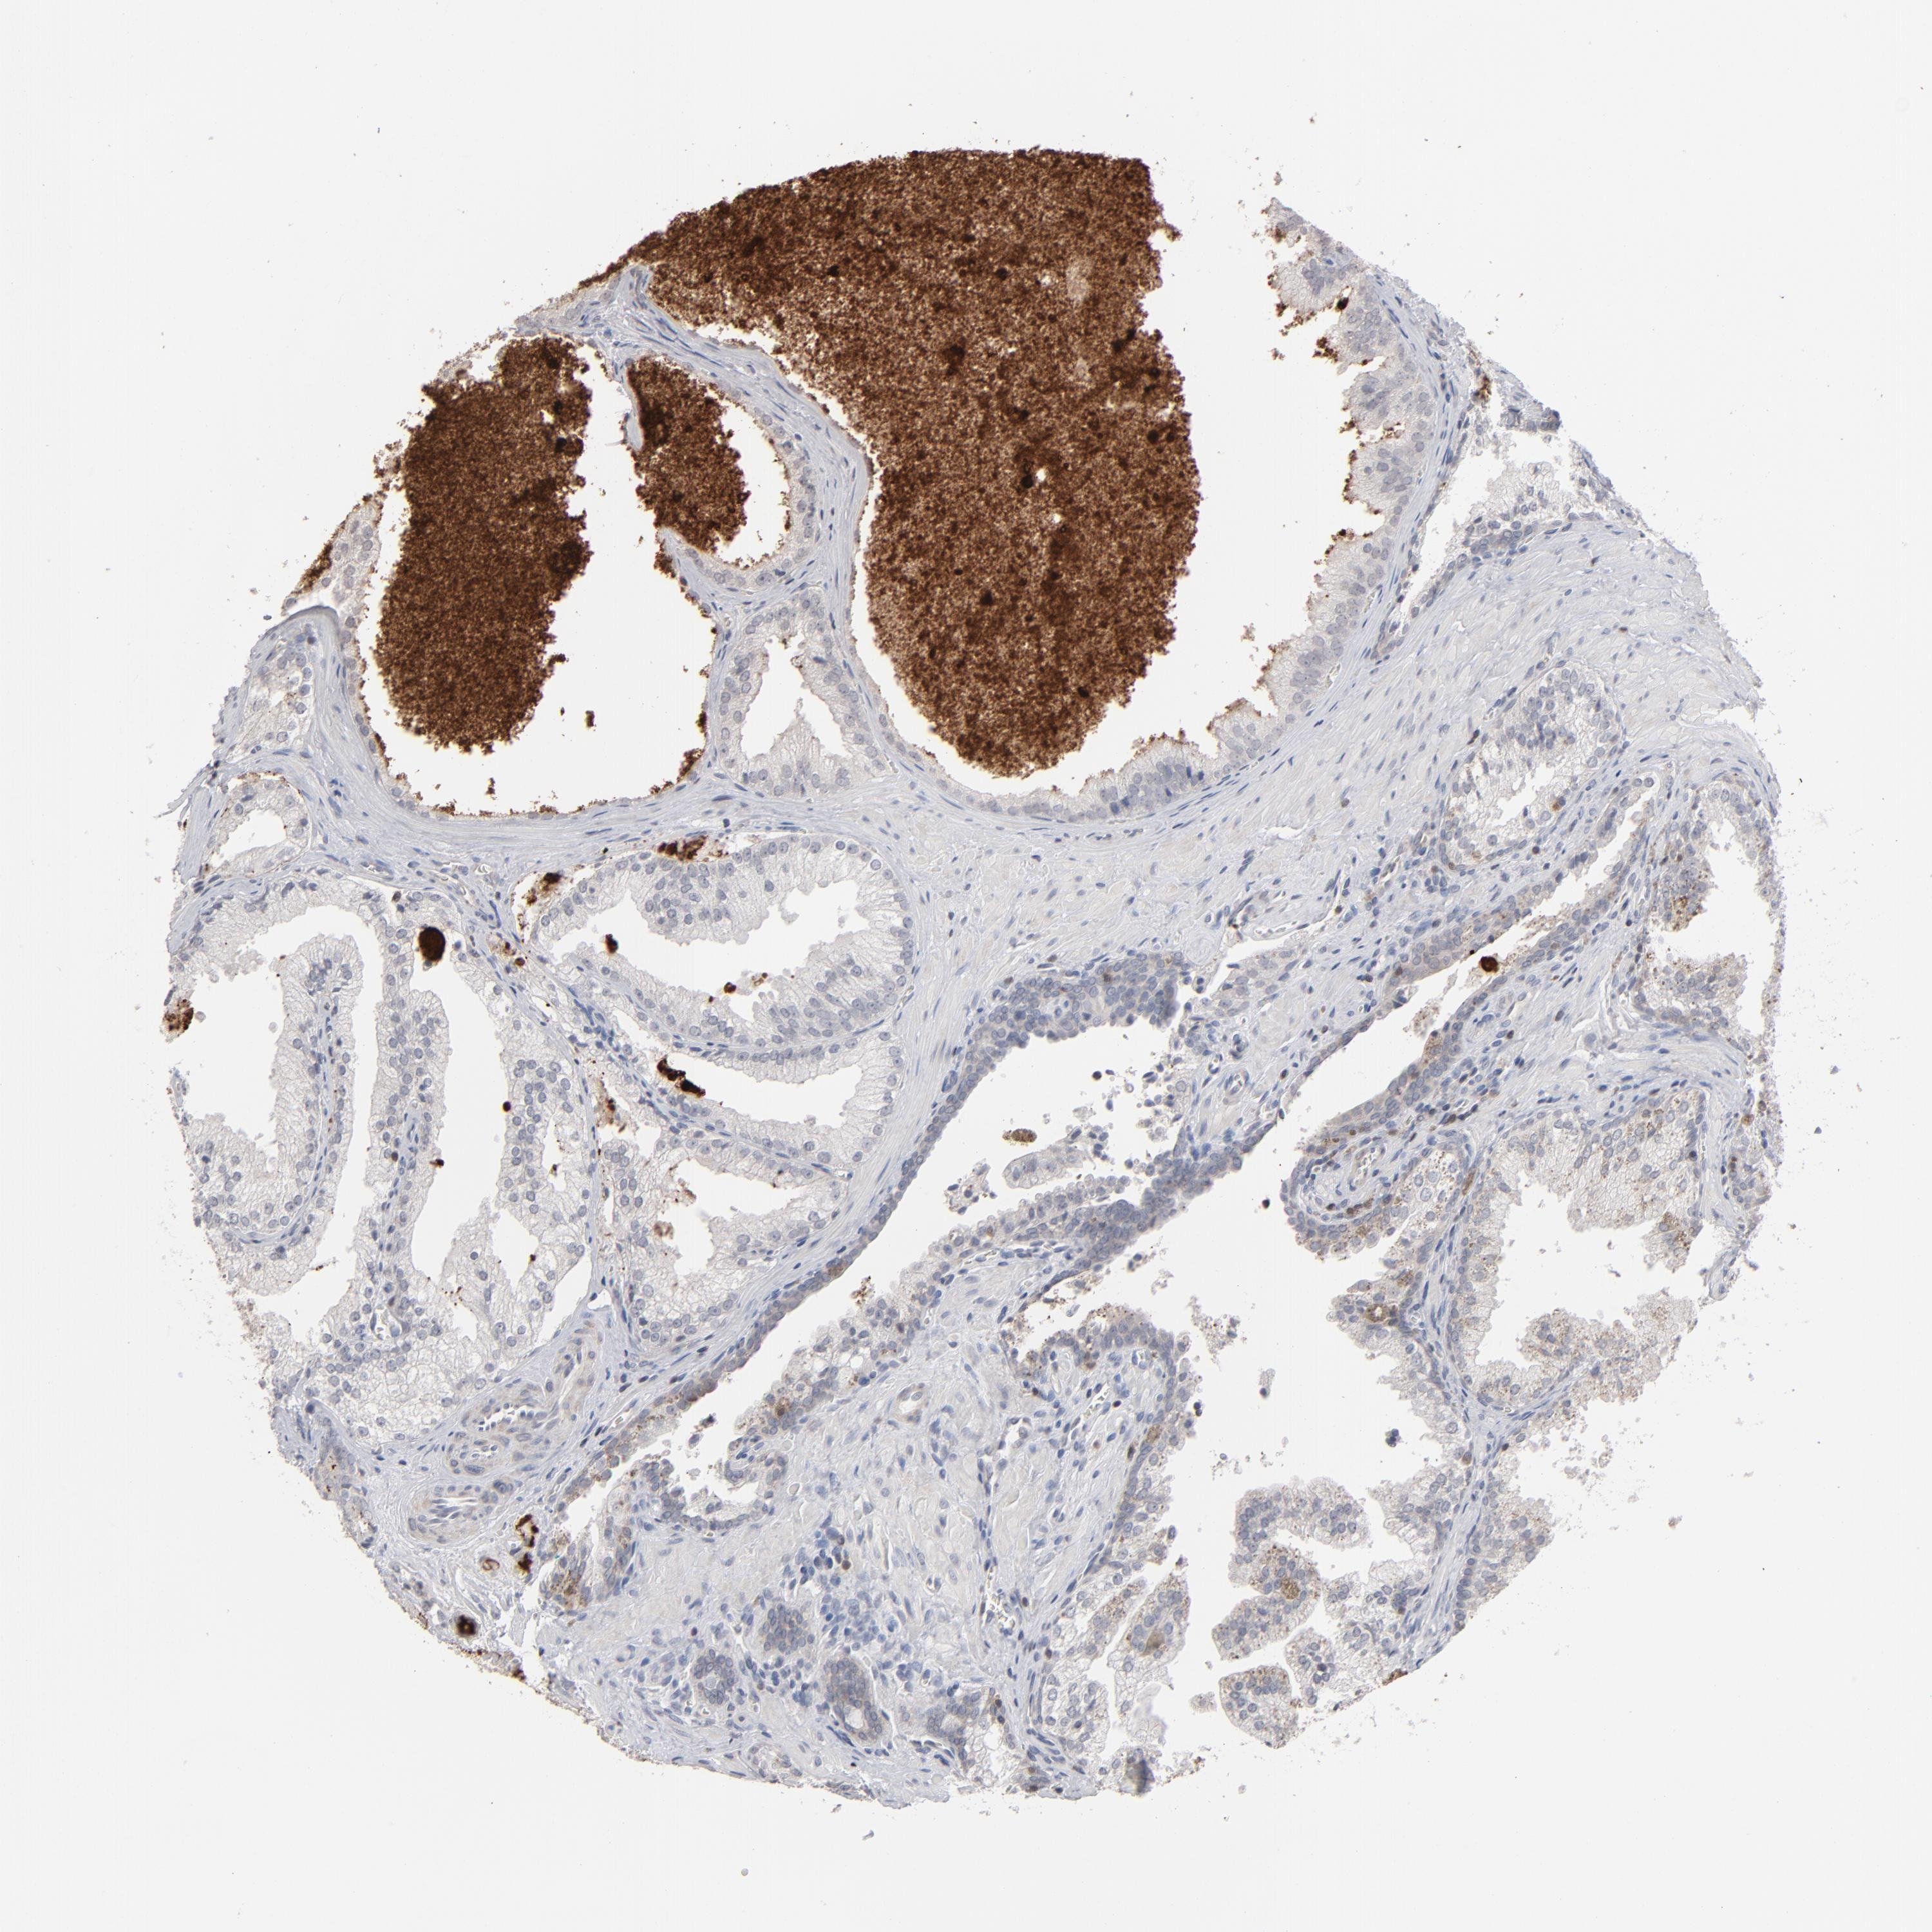

PROSTATE CANCER - Protein expressioni

A mouse-over function shows sample information and annotation data. Click on an image to view it in a full screen mode. Samples can be filtered based on level of antibody staining by selecting one or several of the following categories: high, medium, low and not detected. The assay and annotation is described here.

Antibody stainingi

Antibody staining in the annotated cell types in the current human tissue is reported as not detected, low, medium, or high, based on conventional immunohistochemistry profiling in selected tissues. This score is based on the combination of the staining intensity and fraction of stained cells.

Each image is clickable and will lead to virtual microscopy that enables deeper exploration of all samples and also displays staining intensity scores, fraction scores and subcellular localization as well as patient and tissue information for each sample.

Antibody HPA001860

Antibody CAB013108

Staining

High

Medium

Low

Not detected

Intensity

Strong

Moderate

Weak

Negative

Quantity

>75%

75%-25%

<25%

None

Location

Nuclear

Cytoplasmic/membranous

Cytoplasmic/membranous,nuclear

Adenocarcinoma, Medium grade

Adenocarcinoma, High grade

Adenocarcinoma, Low grade